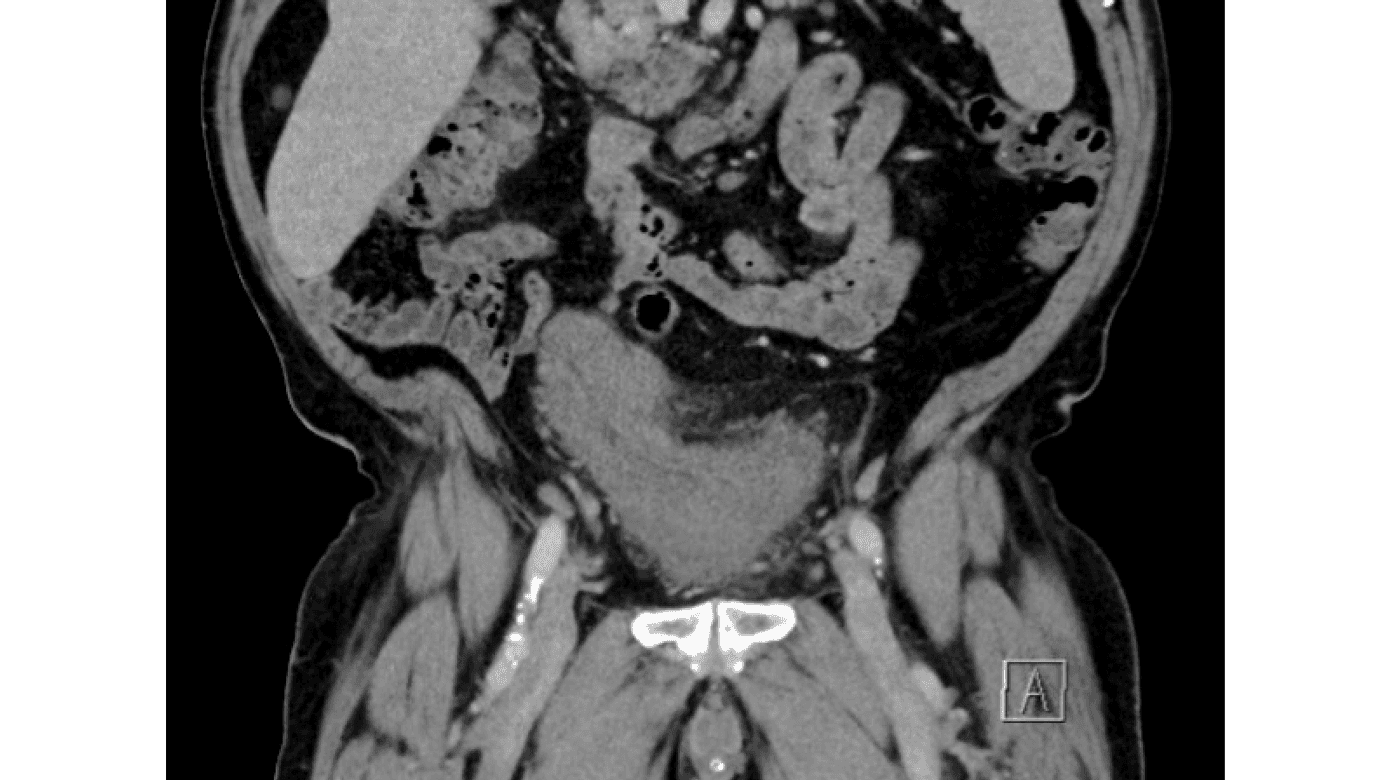

En 72-årig mand blev indlagt til elektiv, venstresidig, total knæalloplastik i CPK. Forud for operationen var han sund og rask og uden medicinering. I forbindelse med afdelingens procedure fik han foretaget en blæreskanning, som viste et umåleligt stort blærevolumen, og han blev efterfølgende engangskateteriseret, hvor blæren udtømtes for 6,2 l urin. Supplerende anamnese var med hyppige, mindre vandladninger gennem længere tid, men ingen smerte, urinvejsinfektionstilfælde, isoleret natlig inkontinens (overløbsinkontinens), hæmospermi, træthed, nedsat appetit eller vægttab.

Efter udskrivelsen fik patienten høj feber og sepsis. Han blev udredt med blandt andet CT for at finde infektionsfokus. Der blev diagnosticeret urosepsis, som blev behandlet, og på grund af bifund opstod mistanke om prostata- og blærecancer. Patienten blev udskrevet, hvorefter urinvejskirurgisk afdeling overtog udredningen og behandlingen af prostatacancer og urinretention.